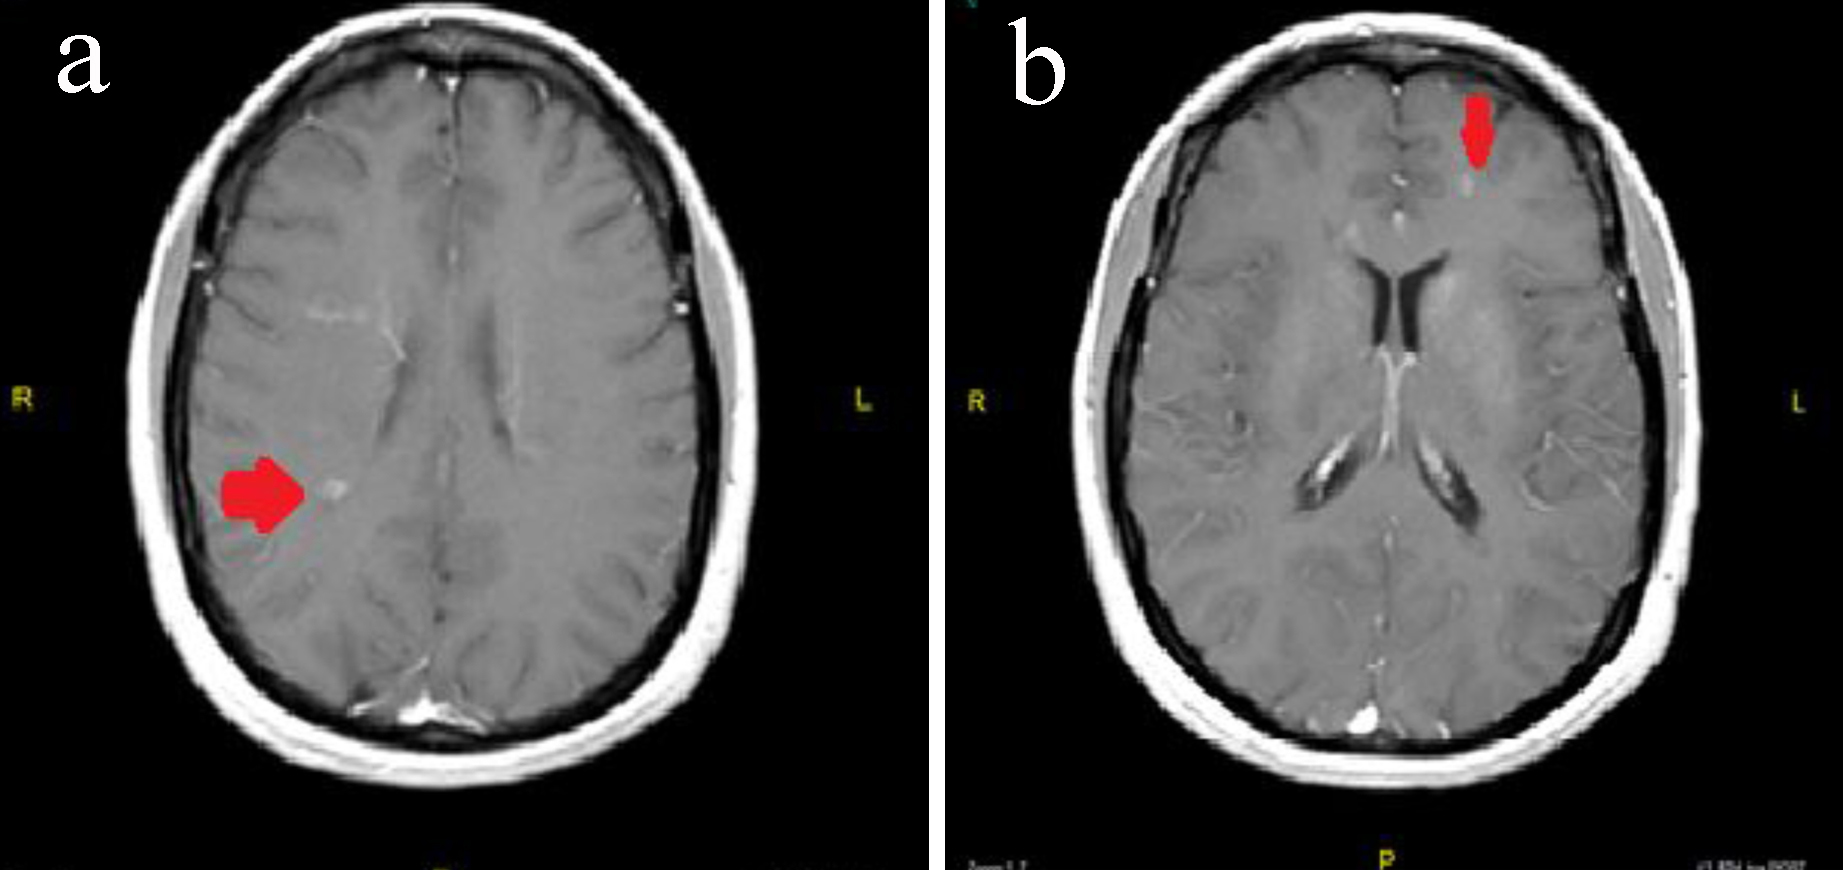

J Neurol Res

https://www.neurores.org/tables/jnr286w-g002.jpg

Figure Brain MRI With And Without Contrast Download Scientific Diagram

https://www.researchgate.net/publication/344282508/figure/fig1/AS:11431281081111555@1661533445082/Figure-Brain-MRI-With-and-Without-Contrast.ppm